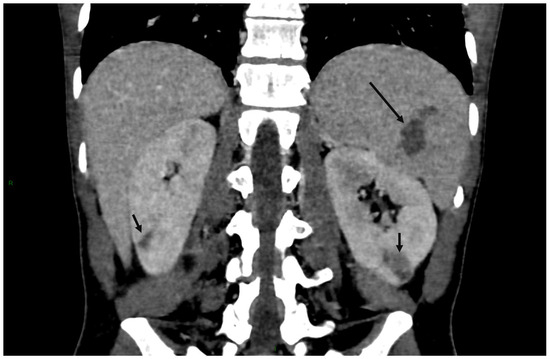

4. Clinical Characteristics of VIAs-Patients